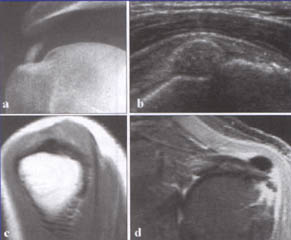

Para el diagnóstico de esta lesión es necesario apoyo radiológico, tanto con una radiografía como una resonancia magnética o mejor aún, una ecografía que muestre el estado actual en el que se encuentra el tendón.